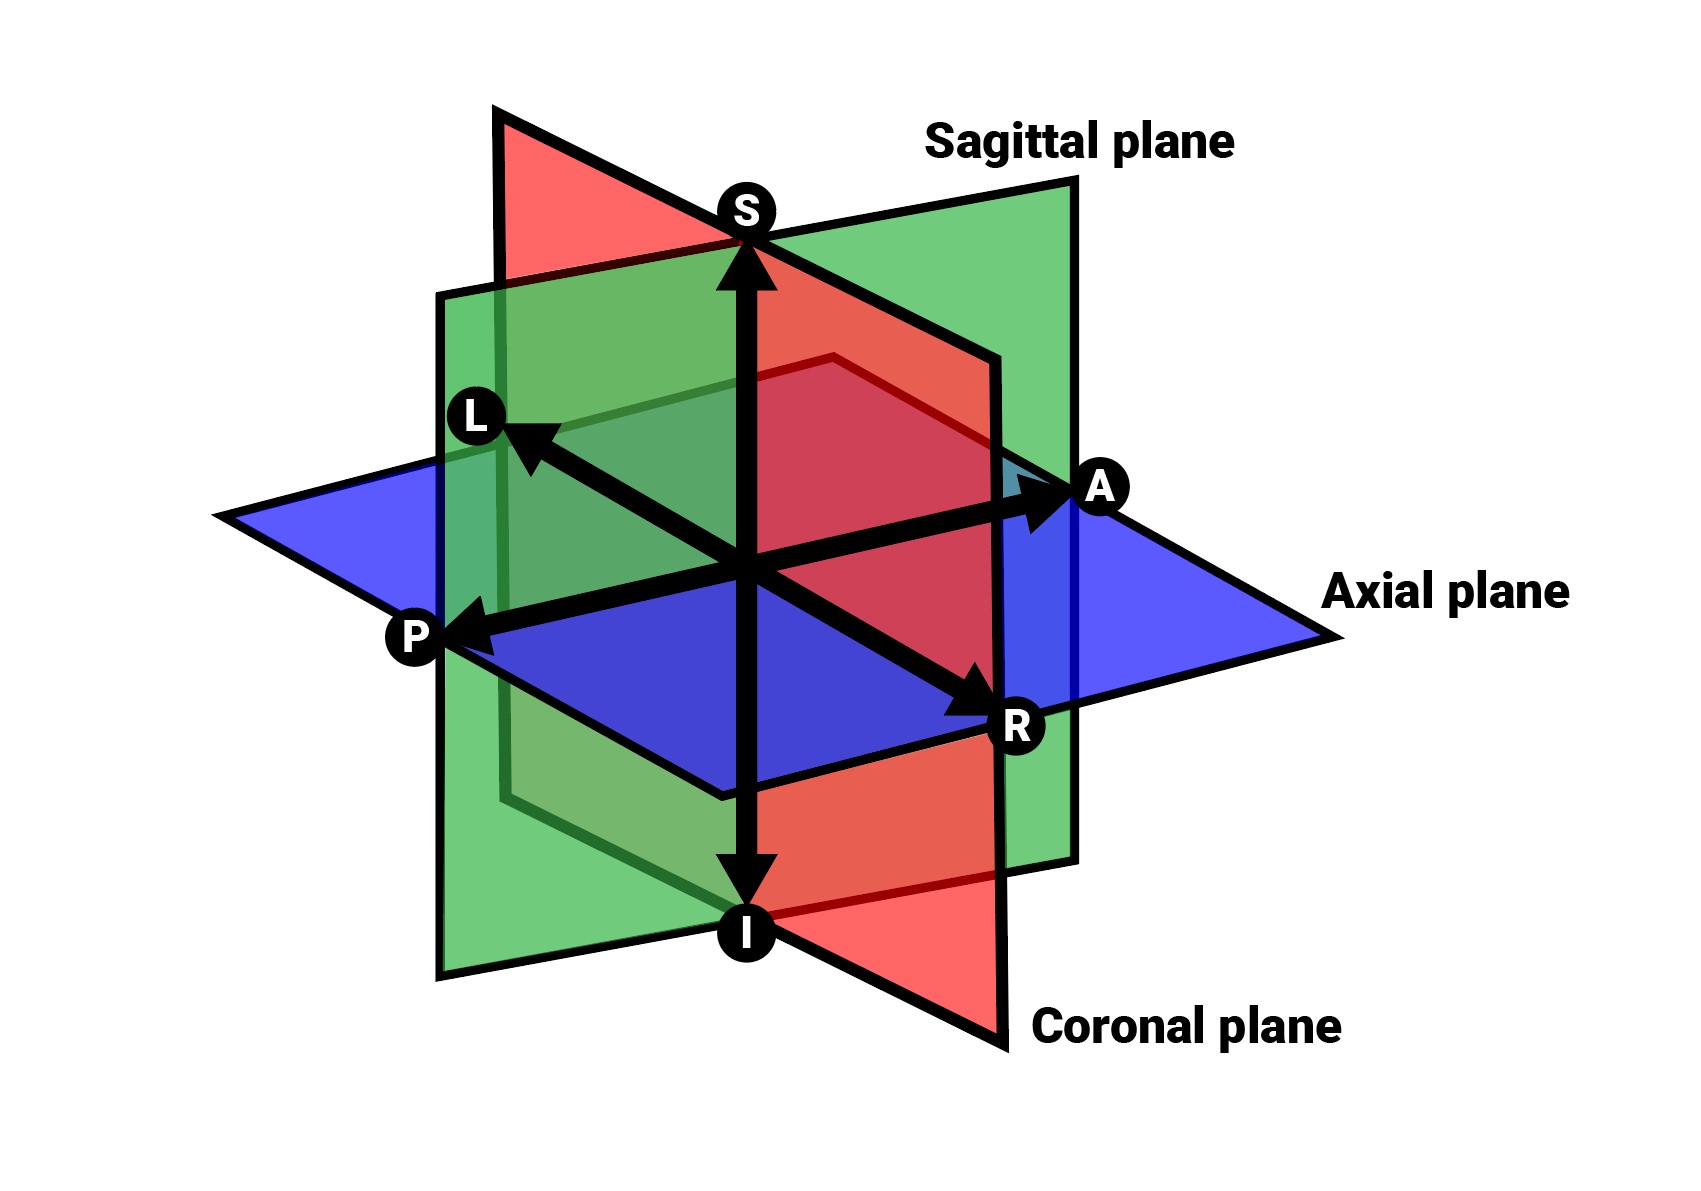

Image Orientation and Image Planes¶

The position and intersection of the other two image planes not represented in the active viewport is indicated by two vertical and horizontal lines called slicers. The endpoints of each slicer are labeled with a letter that corresponds to the appropriate direction/side of the 3D volume, based on the RAS coordinate system.

Only four sides of the available six are indicated on each 2D viewport. The labels and the corresponding side are the following:

Patient Right (R), indicating the right side of the body

Patient Left (L), indicating the left side of the body

Anterior (A), indicating the front side of the body

Posterior (P), indicating the back side of the body

Superior (S), indicating the top side of the body

Inferior (I), indicating the bottom side of the body